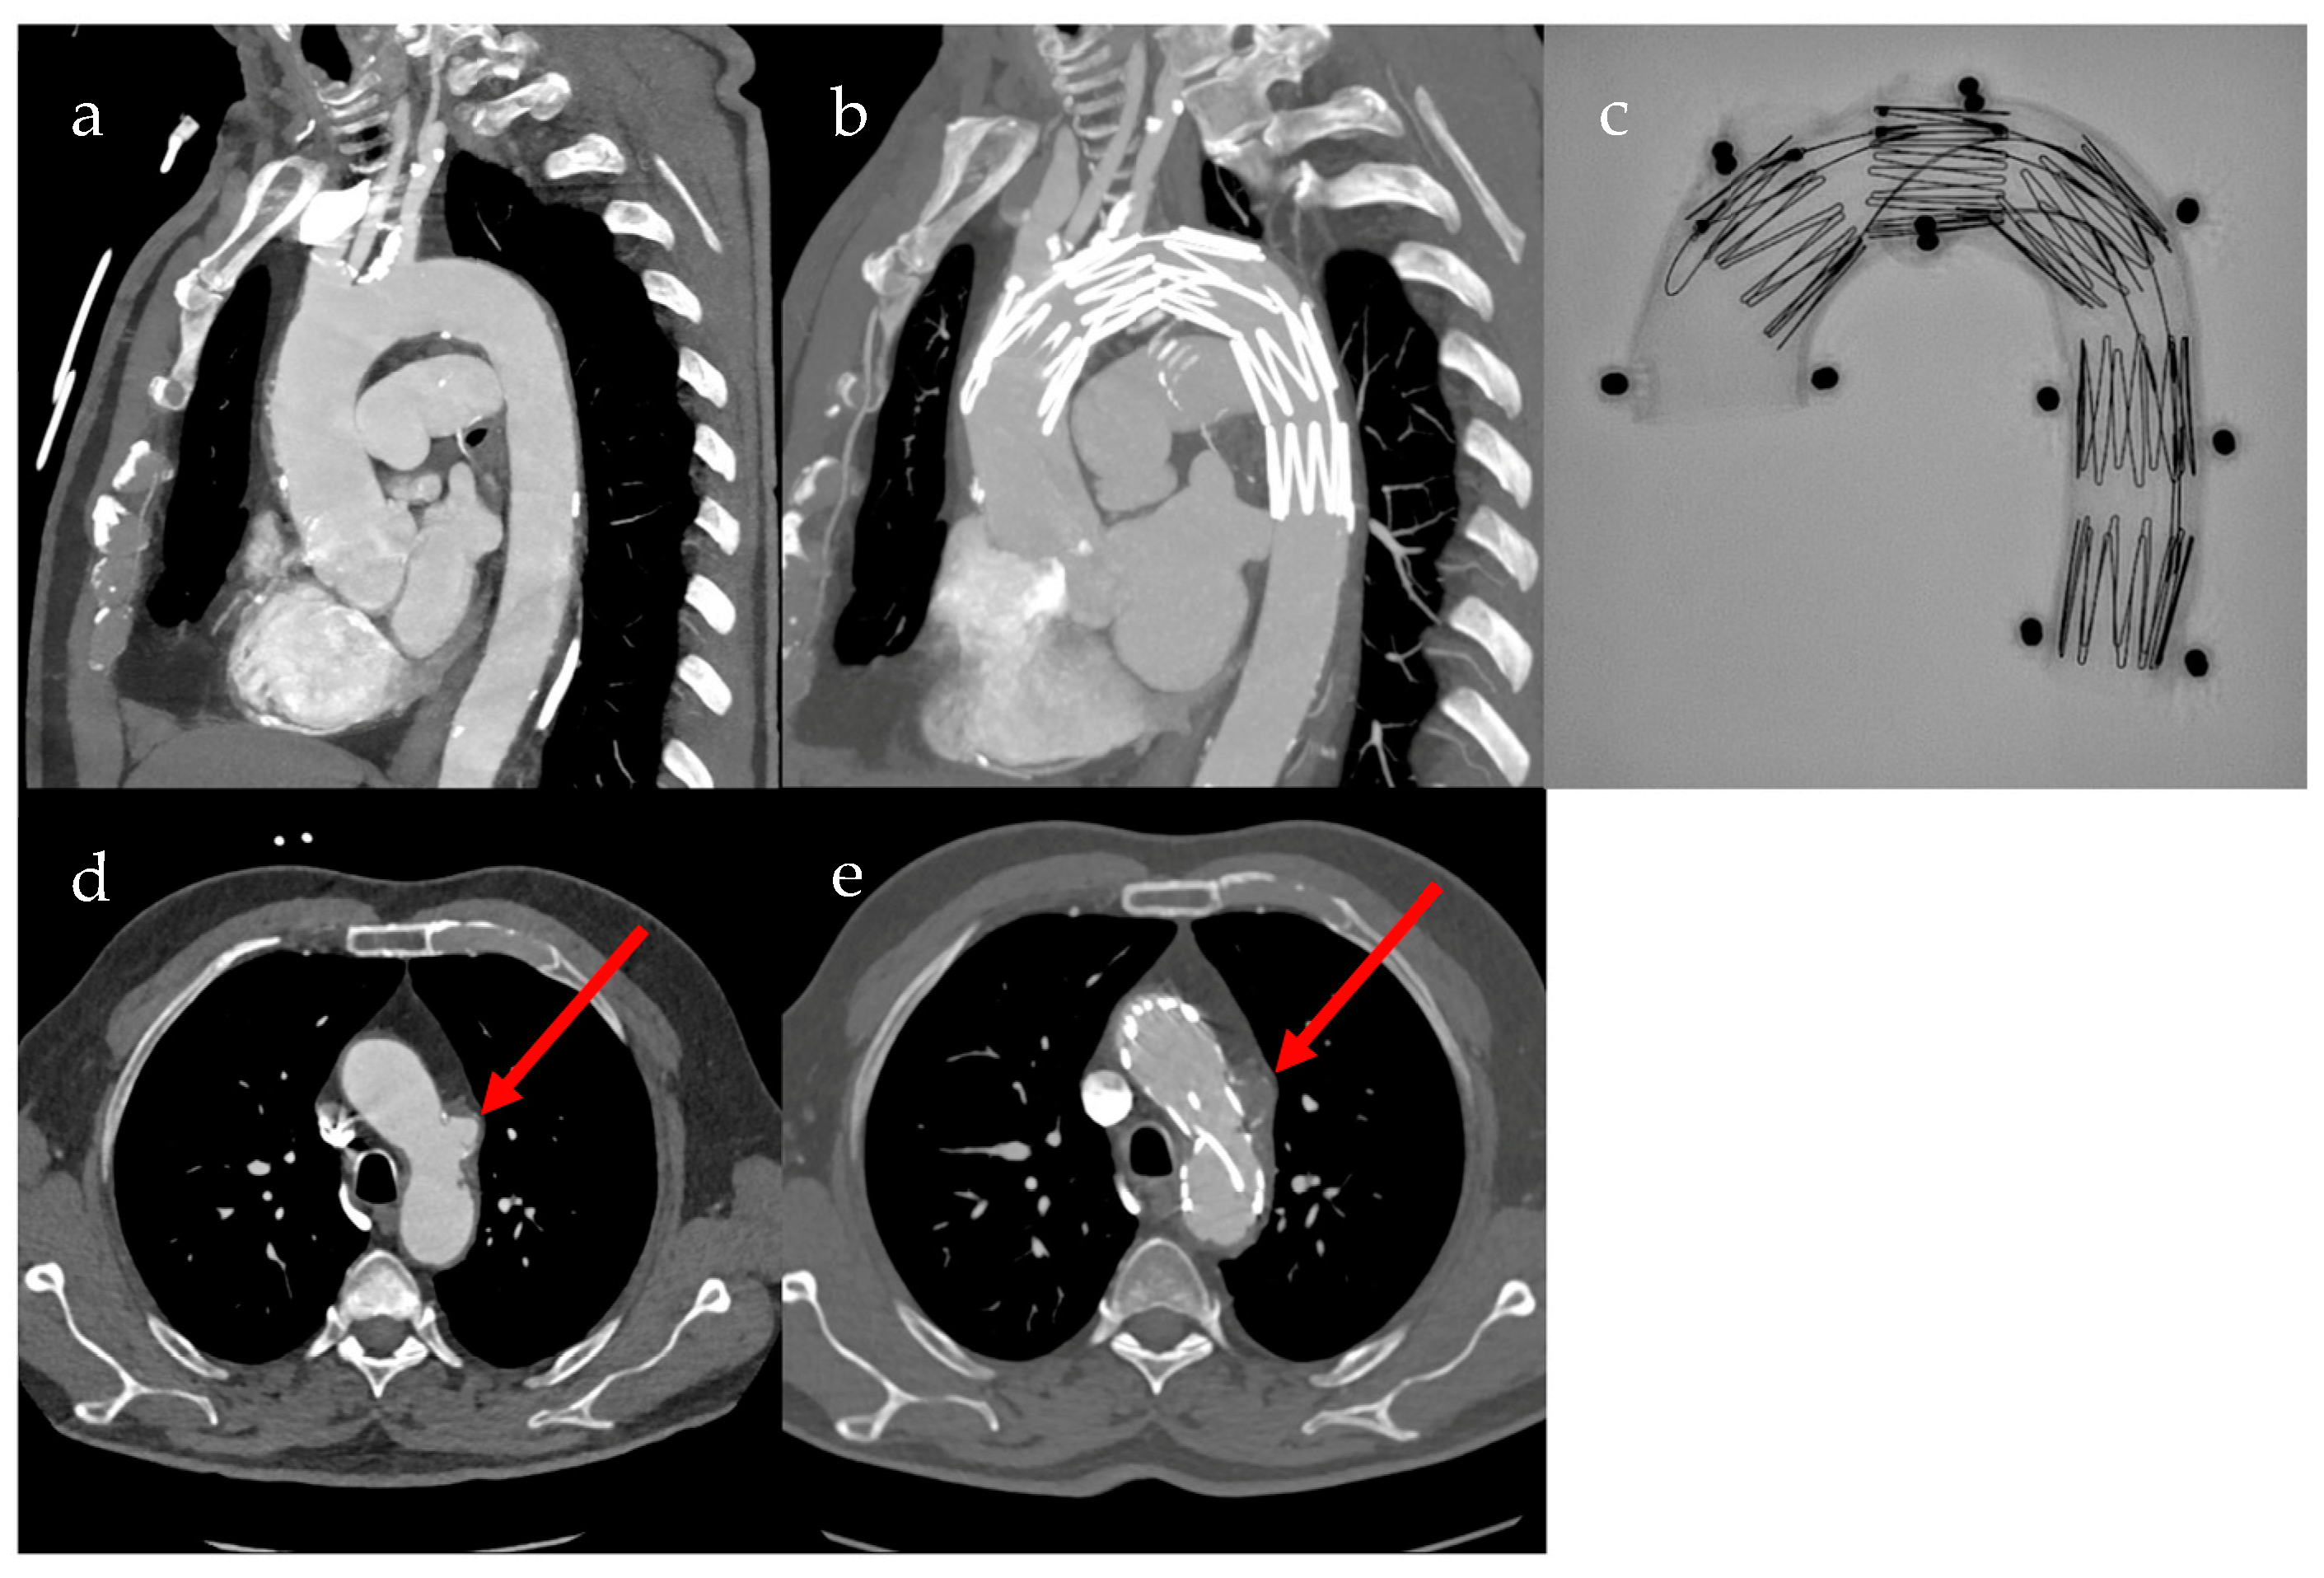

Fenestrated grafts are specialized custom-made fenestrated stent grafts (cmfTEVAR) for the aortic arch to address anatomical challenges associated with standard thoracic stent grafts and extra-anatomic debranching of supra-aortic vessels. Despite technological advancements, aortic arch repairs involving the manipulation of supra-aortic vessels remain challenging and carry the inherent risks of major complications, such as stroke and death. Therefore, the Najuta (Kawasumi Laboratories, Inc., Tokyo, Japan) fenestrated thoracic stent graft, a custom-made solution, was designed to achieve a proximal landing between Zones 0 and 2. This design aims to preserve antegrade flow in supra-aortic vessels, eliminating the need for additional maneuvers in target arteries or the deployment of adjunctive components. The Najuta device represents a bespoke stent graft designed with singular or multiple unsupported fenestrations strategically positioned along its greater curvature to effectively maintain the blood supply through the arch vessels. Pre- and postoperative CT scans of a patient with penetrating aortic ulcer after treatment with cmfTEVAR, as well as an X-ray image of the Najuta fenestrated custom-made stent graft in aortic arch model, are shown in Figure 2 [4].

Figure 2. Pre- and postoperative CT scans of custom-made fenestrated thoracic endovascular aortic repair (cmfTEVAR) using the Najuta stent graft. (a) Sagittal preoperative CT image of the aortic arch; (b) sagittal postoperative CT image of the aortic arch; (c) X-ray image of the Najuta stent graft in aortic arch model; (d) transverse preoperative CT image of the aortic arch, with red arrow showing perfused penetrating aortic ulcer (PAU); (e) transverse postoperative CT image of the aortic arch, with red arrow showing non-perfused PAU.